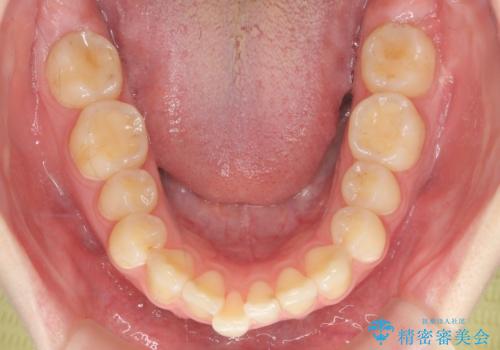

マウスピース矯正で行う出っ歯の治療

- 飛び出したように見える前歯の改善を求めて来院されました。

元々、セラミッククラウンですぐに歯並びを改善したいと希望されていましたが、目立たないマウスピース矯正治療のご提案を行なったところ矯正治療による歯並びの改善を選択されました。

矯正治療を行ったことで出っ歯の改善とともに安定した噛み合わせも手に入れることができました。